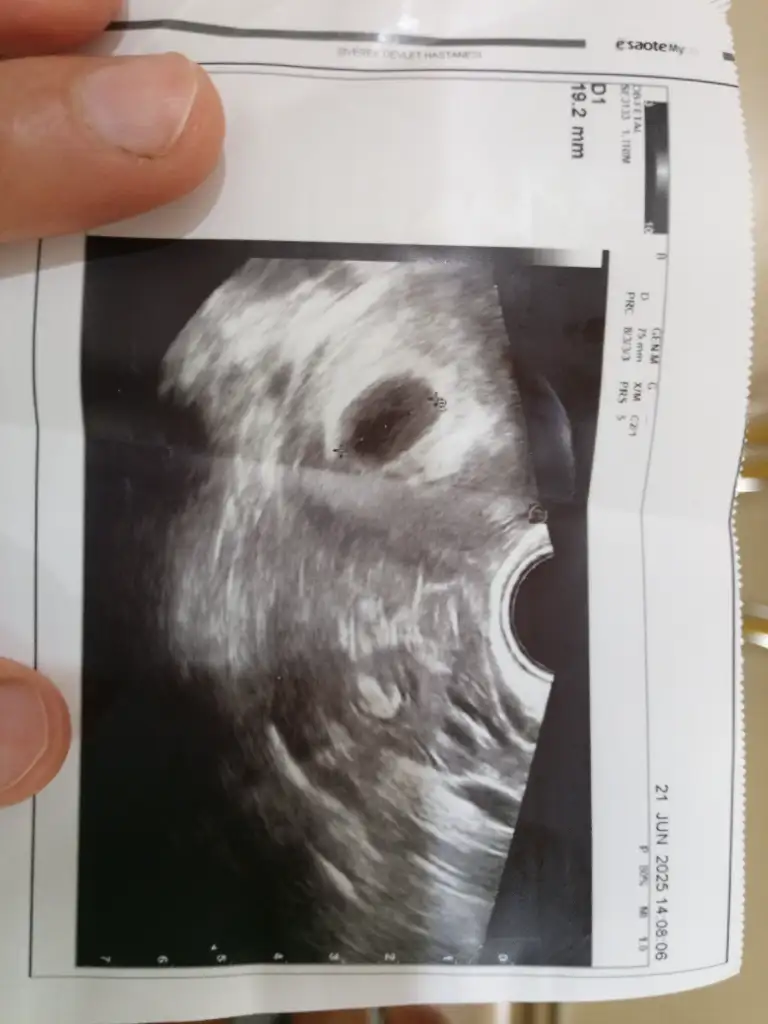

Dün doktor muayenesi oldum karından ultrason bişey görmedi doktor son adet tarihime göre bugün tam 6+1 haftalık Bugün tam 10 gün gecikti adetim neyse muayane oldugumda dediğim gibi karından görmedi bişey, vajinal ultrason baktı keseyi gördü rahim,rahim duvarı arkası mi ne öyle bişey dedi sanırım ondan görmedik karından öyle dedi ve sonra keseyi gördü ama bebek yoktu gibi ya da daha erken mi bilemiyorum kan tahlili istedi+idrar testi ve 2 hafta sonra tekrar gel dedi sizce geç dolenmemi yoksa düşünmek istemediğim dış gebelik mi çok korkuyorum bilgi verir misiniz ?Dün gebelik testi de yaptım pozitif çıktı paylaşacağım altta fotoları yorumlar mısınız lütfen